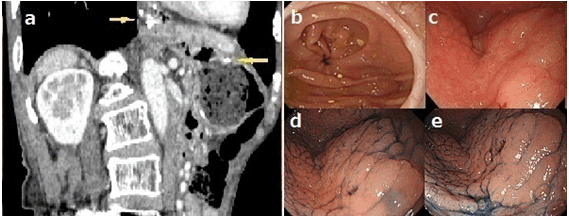

A 75-year-old male had undergone PG with jejunal pouch interposition for mucosal gastric cancer at another hospital, with resultant reflux esophagitis (Figure 3a-b). Approximately five years later, he requested to undergo his first follow-up upper gastrointestinal endoscopy. Physical examination and routine laboratory examinations revealed no abnormalities. Conventional endoscopy and chromoendoscopy with indigo carmine dye showed two separate flat, elevated soft lesions on the distal gastric remnant (Figure 3c-e). The lesion on the proximal side was approximately 25 mm in diameter. The lesion on the distal side was approximately 15 mm in diameter. Biopsy of these lesions revealed well-differentiated adenocarcinoma. Endoscopic ultrasonography was performed to evaluate the invasion depth, and both cancers were classified to be an intramucosal carcinoma with negligible risk of lymph node metastasis. He chose to undergo ESD in response to our explanations, which is similar to Case 1. Curative en bloc resection of both lesions was successfully achieved by ESD using an IT knife-2 and a transparent hood (Figure 4a-e). The procedure time was 150 min. The resected specimen revealed well-differentiated adenocarcinoma confined to the mucosa without vessel infiltrations (Figure 4f). The resection margins were negative. Neither recurrence nor metastasis of GRC has been detected at present, i.e., two years later.

Figure 3: (a) Abdominal computed tomography showed anastomosed parts post-proximal gastrectomy with jejunal pouch interposition (yellow arrows), (b) Conventional view of the anastomosed part post-proximal gastrectomy with jejunal pouch interposition, (c) Conventional view of early gastric cancers, (d) Chromoendoscopic view of the cancer on the proximal side (approximately 25 mm in diameter) stained with indigo carmine, and (e) Chromoendoscopic view of the cancer on the distal side (approximately 15 mm in diameter) separated from the proximal side and stained with indigo carmine.